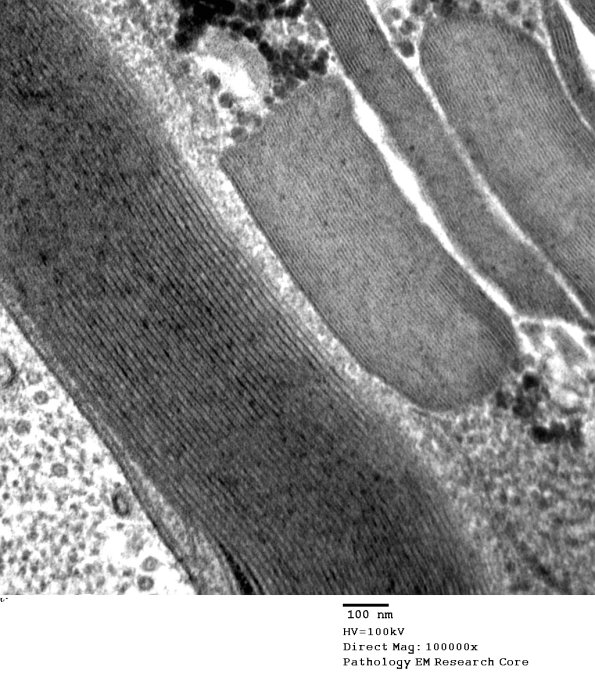

Higher magnification of image #3A2. (electron micrograph)